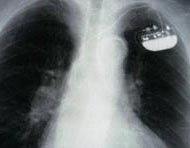

A pacemaker is a small device implanted in the chest. It sends electrical signals to start or regulate a slow heartbeat. It's most often placed in the chest just under the collarbone. A pacemaker may be used if the heart's natural pacemaker (the SA node) is not working correctly, causing a slow heart rate or rhythm, or if the electrical pathways are blocked.

Front view of male chest showing pacemaker.